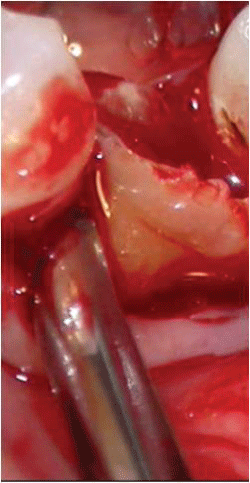

2- After 14 days, the edges of the wound were revived and the extraction of the tooth 38 (which would be transplanted), was held. However, the pericoronal hood was maintained together with the tooth (Figure 4 and Figure 5).

Figures 5: Atraumatic extraction of the tooth 38, the pericoronal hood was maintained together with the tooth.